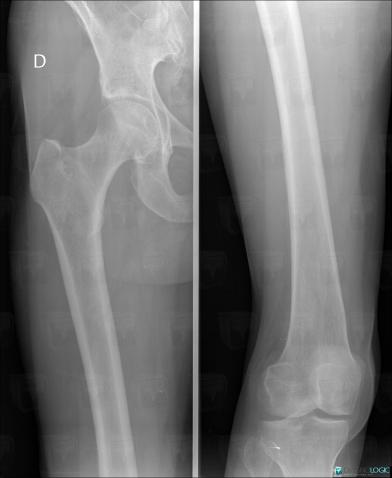

Ewing sarcoma, Femur - Mid part, X rays

Here is the specific information in the key image above:

- Diagnosis Ewing sarcoma, Location(s) Femur - Mid part, with gamuts